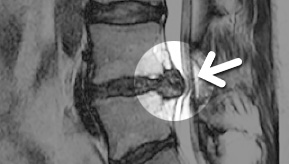

MRI

MRI ġ